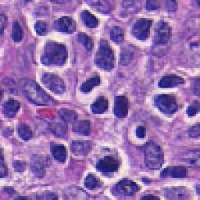

Medical Diagnostics & Research: Researchers and healthcare providers can use LDANN-BASIC to assist in the identification of lymphocyte classes, helping to diagnose diseases like leukemia or lymphoma more efficiently and enhancing our understanding of the immune system.

Pharmaceutical Development & Drug Testing: The model can be employed in pharmaceutical labs to study the effects of new drugs on lymphocyte populations, contributing to the development of more effective medications or therapies targeting specific immune conditions.

Automated Clinical Laboratory Systems: LDANN-BASIC can be integrated into automated image analysis workflows within clinical laboratories, streamlining the process of analyzing patient samples and reducing the risk of human error in lymphocyte classification.

Educational Purposes: The model can serve as a teaching tool for medical students, clinical laboratory scientists, and immunology researchers to learn and visually understand different types of lymphocytes, thereby improving their skills and knowledge in the field of histology and pathology.

Remote and Telemedicine Diagnostics: LDANN-BASIC can be used in remote healthcare settings or telemedical diagnostic systems, enabling healthcare professionals to analyze blood samples from patients even if they are located in rural or remote areas with limited access to specialized labs.